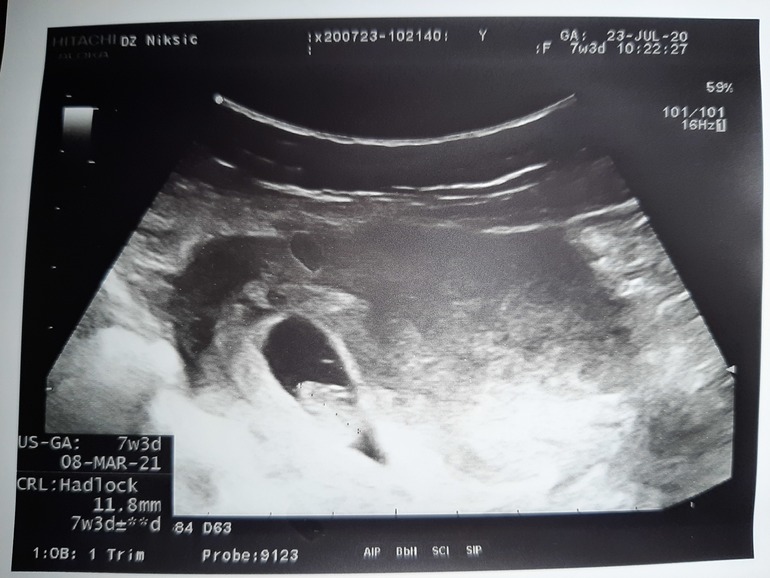

Хоть и почитала о методе Рамзи, что его точность вместо заявленных 97.2% на практике всего-лишь 50/50, все же спрошу у вас, мамочки со стажем, что видите на моем снимке - девочку или мальчика? Лично я не поняла, что именно надо смотреть, вернее, где искать хорион...🤨 Да, УЗИ абдоминальное.

Срок 7+3, и по УЗИ, и по ПМ. Может быть, аппарат не супер современный, фотка нечеткая.